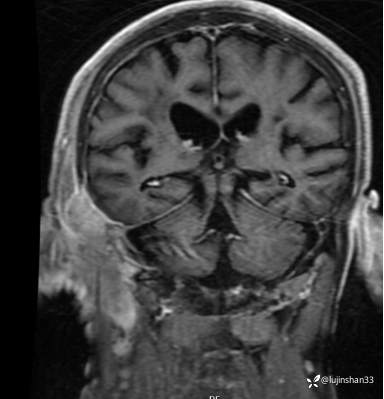

简要病史:患者2022年10月掏耳后出现右耳疼痛,流水,伴血性分泌物,伴听力下降,无头痛头晕,无口角歪斜,自行购买滴耳液及口服罗红霉素,效果不佳。后右耳痛加剧,偶需止疼药治疗。后于XXXXXX医院行中耳乳突CT检查示“右耳恶性肿瘤?坏死性外耳道炎?”颅脑磁共振平扫示“脑内多发缺血灶、梗塞灶,脑白质疏松,脑萎缩、右中耳恶性占位。”建议上级医院治疗。2023-4-13就诊于我科门诊,行右外耳道病理活检示“鳞状上皮黏膜慢性炎伴急性炎,可见较多炎性坏死,部分上皮增生明显伴不典型增生,小灶上皮呈重度异型增生伴癌变。”建议手术治疗。今患者为求进一步诊治,门诊以“颞骨占位(右)“收治入院。

MRI:

右侧颞骨鳞癌(T4)